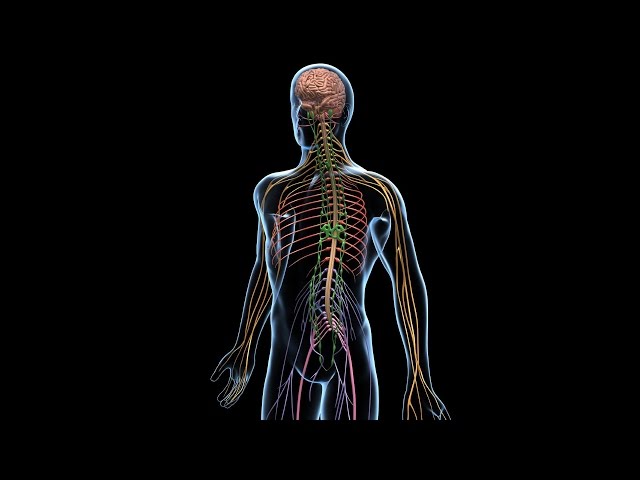

Доказано, что паразиты (или глисты, как их называют в народе) способны поражать и “заселять” любые органы человека, включая глаза, мозг, сердце.

Доказано, что токсины, выделяемые гельминтами, негативно воздействуют на нервную систему зараженного человека, что проявляется раздражительностью, частыми перепадами настроения, апатией, депрессией, снижением концентрации внимания и памяти.

В тяжелых случаях возможно отравление продуктами жизнедеятельности паразитов головного мозга, что может спровоцировать судороги.

Везде. Они могут селиться в любых органах, в мышцах, суставах, костях, крови, лимфе, сперме. Нет ни одной среды, которая бы не поражалась.

Чем серьёзнее глистная инвазия больного, тем больше вредных веществ выделяют паразиты. Это губительно влияет на самочувствие и нервную систему взрослых и детей. Пример тому — мигрень, головокружение, боли в суставах.